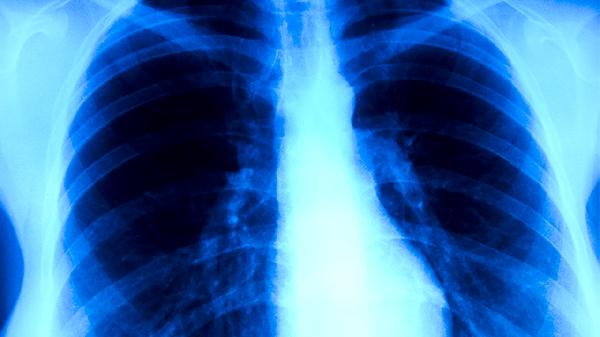

肺结核可通过异烟肼片、利福平胶囊、吡嗪酰胺片、乙胺丁醇片、链霉素注射液等药物治疗。肺结核通常由结核分枝杆菌感染引起,表现为咳嗽、咳痰、低热、盗汗等症状。

肺结核患者应保证充足营养摄入,每日补充优质蛋白如鸡蛋、鱼肉,多吃富含维生素的新鲜蔬菜水果。保持居室通风良好,咳嗽时掩住口鼻,痰液需消毒处理。治疗期间严格遵医嘱按时服药,完成6-9个月全程治疗以防复发,定期复查胸部影像学和痰菌检测。出现药物不良反应或症状加重时需及时就医调整方案。